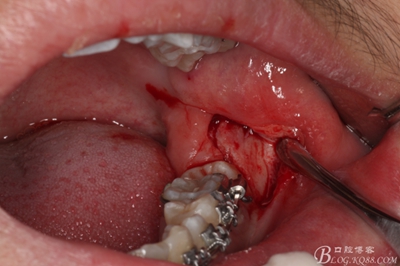

圖14.先取出遠(yuǎn)中部分。

14_副本.jpg

圖15.接著取出近中部分

15_副本.jpg

圖16.清理38牙槽窩內(nèi)的囊壁及碎牙片

16_副本.jpg

圖17.   38牙槽窩放入膠質(zhì)銀

17_副本.jpg

18.縫合

18_副本.jpg